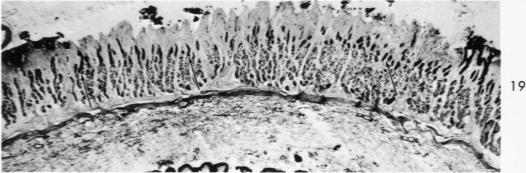

Histochemical and morphologic changes in gastric mucosa of dogs on ulcerogenic regimen.

Am J Pathol. 1969 Jul;56(1):129-51.